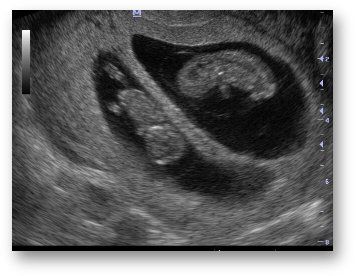

GRAVIDANZA GEMELLARE

Corionicità

Con questo termine ci si riferisce al numero di placente in una gravidanza gemellare.

- gravidanza monocoriale: gravidanza gemellare con una unica placenta (20%),

- gravidanza bicoriale: gravidanza gemellare con due placente distinte (80%).

È molto importante fare questa distinzione (con ecografia in epoca precoce della grravidanza), in quanto, essendo le gravidanze monocoriali interessate da maggiori complicazioni, richiedono un controllo medico molto più accurato.

Amnioticità

Con questo termini ci si riferisce al numero delle cavità amniotiche. Pertanto di parla di:

- gravidanza monoamniotica: quando i feti sono entrambi in un unico sacco amniotico,

- gravidanza biamniotica: quando i feti sono in due sacchi amniotici distinti.